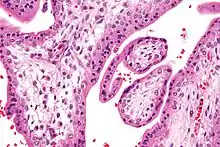

Micrograph showing chorionic villi. Intermediate magnification. H&E stain.